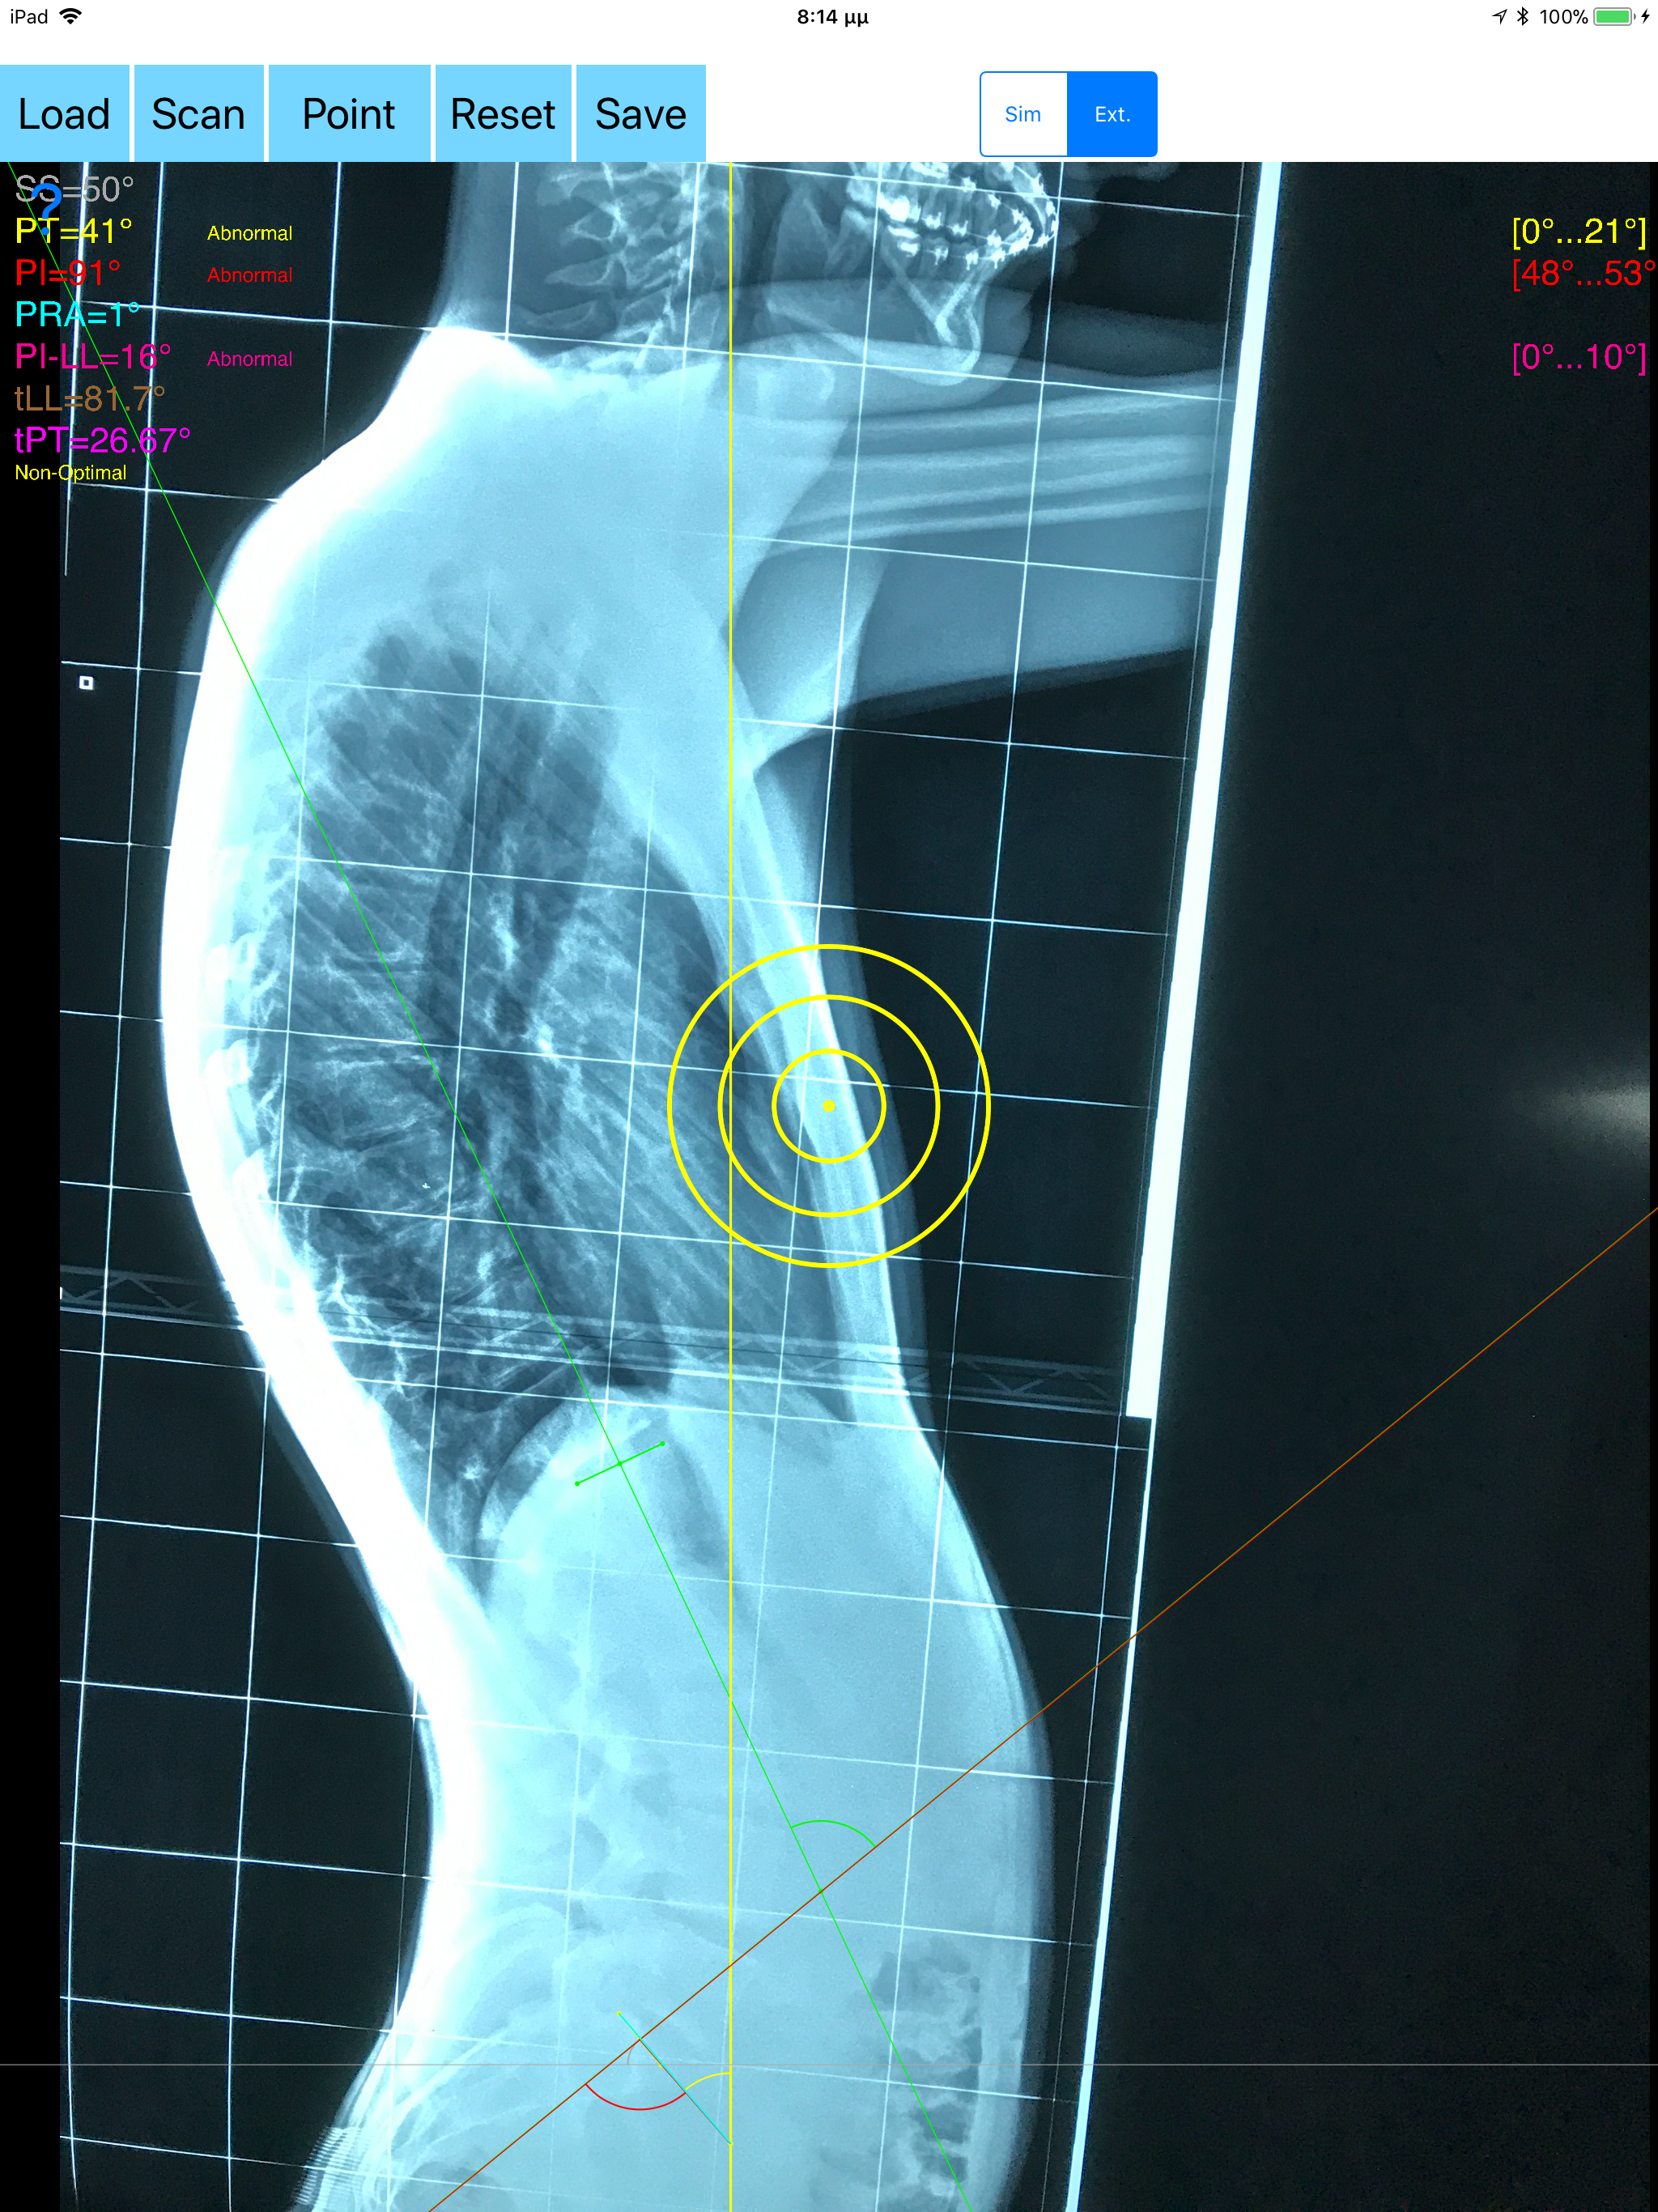

The assessment of the parameters involved in spinopelvic jucture are of paramount importance for spine and joint replacement surgeon. The dynamic interplay between flexibility and balance around the axis of gravity determine the type and the amount of influence in spine and hips. Radiographic parameters to evaluate objectively the spinopelvic sagittal balance are Pelvic incidence (PI), Sacral slope (SS), Pelvic Tilt (PT), Lumbar lordosis (LL). Drawings in patients X-rays and precise measurements are important in order to quantify the magnitude of spinal deformities, to monitor the success or failure of treatment and thus optimise the management of patients according to the severity of the imbalance or even to identify patient at risk of degenerative spondylolisthesis or disk herniation. The Spinopelvic Balance App is medical software aimed for orthopaedic surgeons, providing tools that allow doctors to: -Securely import medical images directly from the camera or stored photos. -By marking few points at the image of X-ray, the App calculates and offers a very convenient way to determine the most accurate possibly way at once, Pelvic incidence (PI), Sacral slope (SS), Pelvic Tilt (PT), Lumbar lordosis (LL), thoracic kyphosis, PI–LL Pelvic incidence Angle (PI) minus Lumbar lordosis Angle (LL) PI–LL, theoretical normal pelvic tilt (tPT),theoretical normal L1-S1 lumbar lordosis (tL1S1), Pelvic Radius Angle (PRA). According to measured parameters the app categorises the severity of the imbalance of spine, in different stages: optimal or non optimal. -Save the planned images, for later review or consultation.The measured values are compared by normal reference databases and also data are exported as txt file, ready to print or to input as cells to excel for research. -The app allows choosing between simple and extended method according to everyday preference and also by choosing points in vertebra body in a independent manner from order. -The app can be used to measure L5 Incidence (L5I) Angle or L4 respectively. -The app offers theoretical value estimation this is particularly useful because a sensible difference between theoretical value and measured value reveals a compensation phenomenon if the pelvis tilt (PT) is higher than its theoretical value, then it is due to pelvis retroversion, which is a compensation phenomenon. Knowing the theoretical value of Pelvis Tilt (PT) provided it is easy to understand that a sensible difference between theoretical value and measured value is a compensation phenomenon. All information received from the software output must be clinically reviewed regarding its plausibility before patient treatment! Spinopelvic Balance App indicated for assisting healthcare professionals. Clinical judgment and experience are required to properly use the software.The software is not for primary image interpretation. In a busy everyday practice, the examiner have to draw lines in X-rays or in clinical settings, this it is time consuming and cumbersome. Accessory instruments like protractors, hinged goniometers, well sharped pencils, rulers or even transparent papers must be available. The app offers a very convenient and accurate way to perform most common radiographic measurements for spine, at the spinopelvic juncture in a blink of an eye in front of your screen. The build in feature of the app, allows results to be categorized may help decide what could be considered normal or pathologic. The app is not a simple goniometer, is an enhanced product which helps to monitor objectively the course of the treatment and evaluate optimally the spine. This App is particular useful in clinical settings where you need a quick results without losing time.Please see tutorial videos at the developer’s web Reference 1.Nunes VR, et al.Spinopelvic balance evaluation of patients with degenerative spondylolisthesis L4L5 and L4L5 herniated disc who underwent surgery.Rev Bras Ortop. 2016 Sep 22;51(6):662-666.